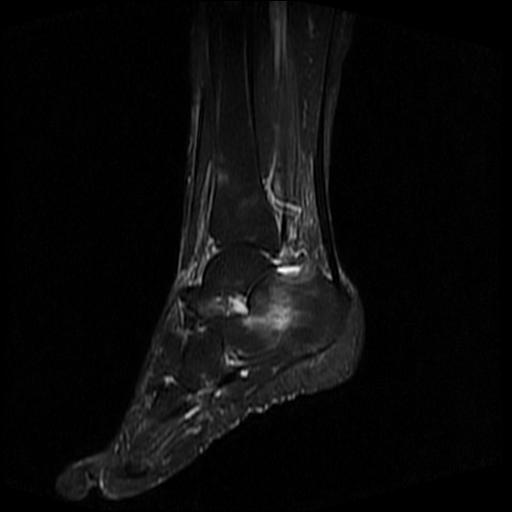

标题: MRI0968:女性,70岁,跟骨信号异常 [打印本页]

标题: MRI0968:女性,70岁,跟骨信号异常

女性,70岁,右侧跟骨疼痛2个月,负重时加剧,不负重时不疼。

胫骨下段,跟骨、距骨可见斑片状异常信号区;考虑:转移瘤

跟骨长t1长t2信号异常,边缘模糊(肿瘤一般边界清楚,故肿瘤不考虑),压脂像呈高信号--骨髓水肿(炎症?)。